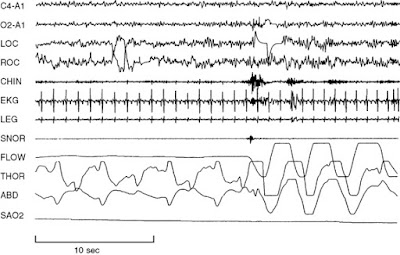

Jeden kanał EEG (centralny z odniesieniem do słuchu) jest używany do monitorowania etapu snu. Jednak większość laboratoriów korzysta z 2 kanałów centralnych i 2 kanałów potylicznych, a odniesienia do kanału z odniesieniem do słuchu są pomocne w identyfikacji opóźnienia snu i wybudzeń. W celu określenia lokalizacji tych kanałów stosuje się system rozmieszczenia 10-20 elektrod. Dodatkowe kanały EEG mogą być wykorzystywane, szczególnie u pacjentów z padaczką.

Dwa kanały EOG są wykorzystywane do monitorowania zarówno poziomych, jak i pionowych ruchów oczu. Elektrody umieszczone są po prawej i lewej stronie, jedna powyżej i jedna poniżej poziomej osi oka. Ocena ruchów gałek ocznych jest konieczna z 2 powodów. Pierwszym z nich jest dokumentowanie początku fazy szybkich ruchów gałek ocznych (REM), a drugim jest odnotowanie obecności wolnoobrotowych ruchów gałek ocznych, które zazwyczaj towarzyszą początkowi snu.

Jeden kanał EMG (zazwyczaj podbródek) jest używany do rejestrowania atonii mięśniowej podczas snu REM lub braku atonii u pacjentów z parazynomniami związanymi z REM. Aby ocenić bruksizm, elektrody EMG można umieścić także nad żwaczem. Rejestracja EMG z innych grup mięśni jest oceniana pod kątem innych zaburzeń snu. Na przykład EMG kości piszczelowej przedniej jest pomocne w ocenie okresowych ruchów kończyn podczas snu, a EMG międzyżebrowe jest wykorzystywane jako pomoc w określaniu wysiłku podczas zdarzeń związanych z oddychaniem.

Dwa kolejne kanały służą do monitorowania przepływu powietrza. Jeden kanał termistorowy (ustny i/lub nosowy) służy do oceny obecności lub braku przepływu powietrza. Każda zmiana temperatury w miarę jak pacjent wdycha i wydycha prowadzi do powstania sygnału, więc ten kanał jest niewrażliwy na tylko częściową blokadę przepływu. Termistor jest zalecanym kanałem do oceny bezdechu. Kanał przetwornika ciśnienia w nosie jest bardziej czułą miarą ograniczenia przepływu powietrza. Normalne oddychanie ma zaokrąglony wzór, podczas gdy opór przepływu powietrza prowadzi do wyrównania sygnału przepływu. Przetwornik ciśnienia jest zalecanym kanałem do oceny spłyceń oddechu. Jest on również stosowany do oporu przepływu powietrza w zespole oporu górnych dróg oddechowych.